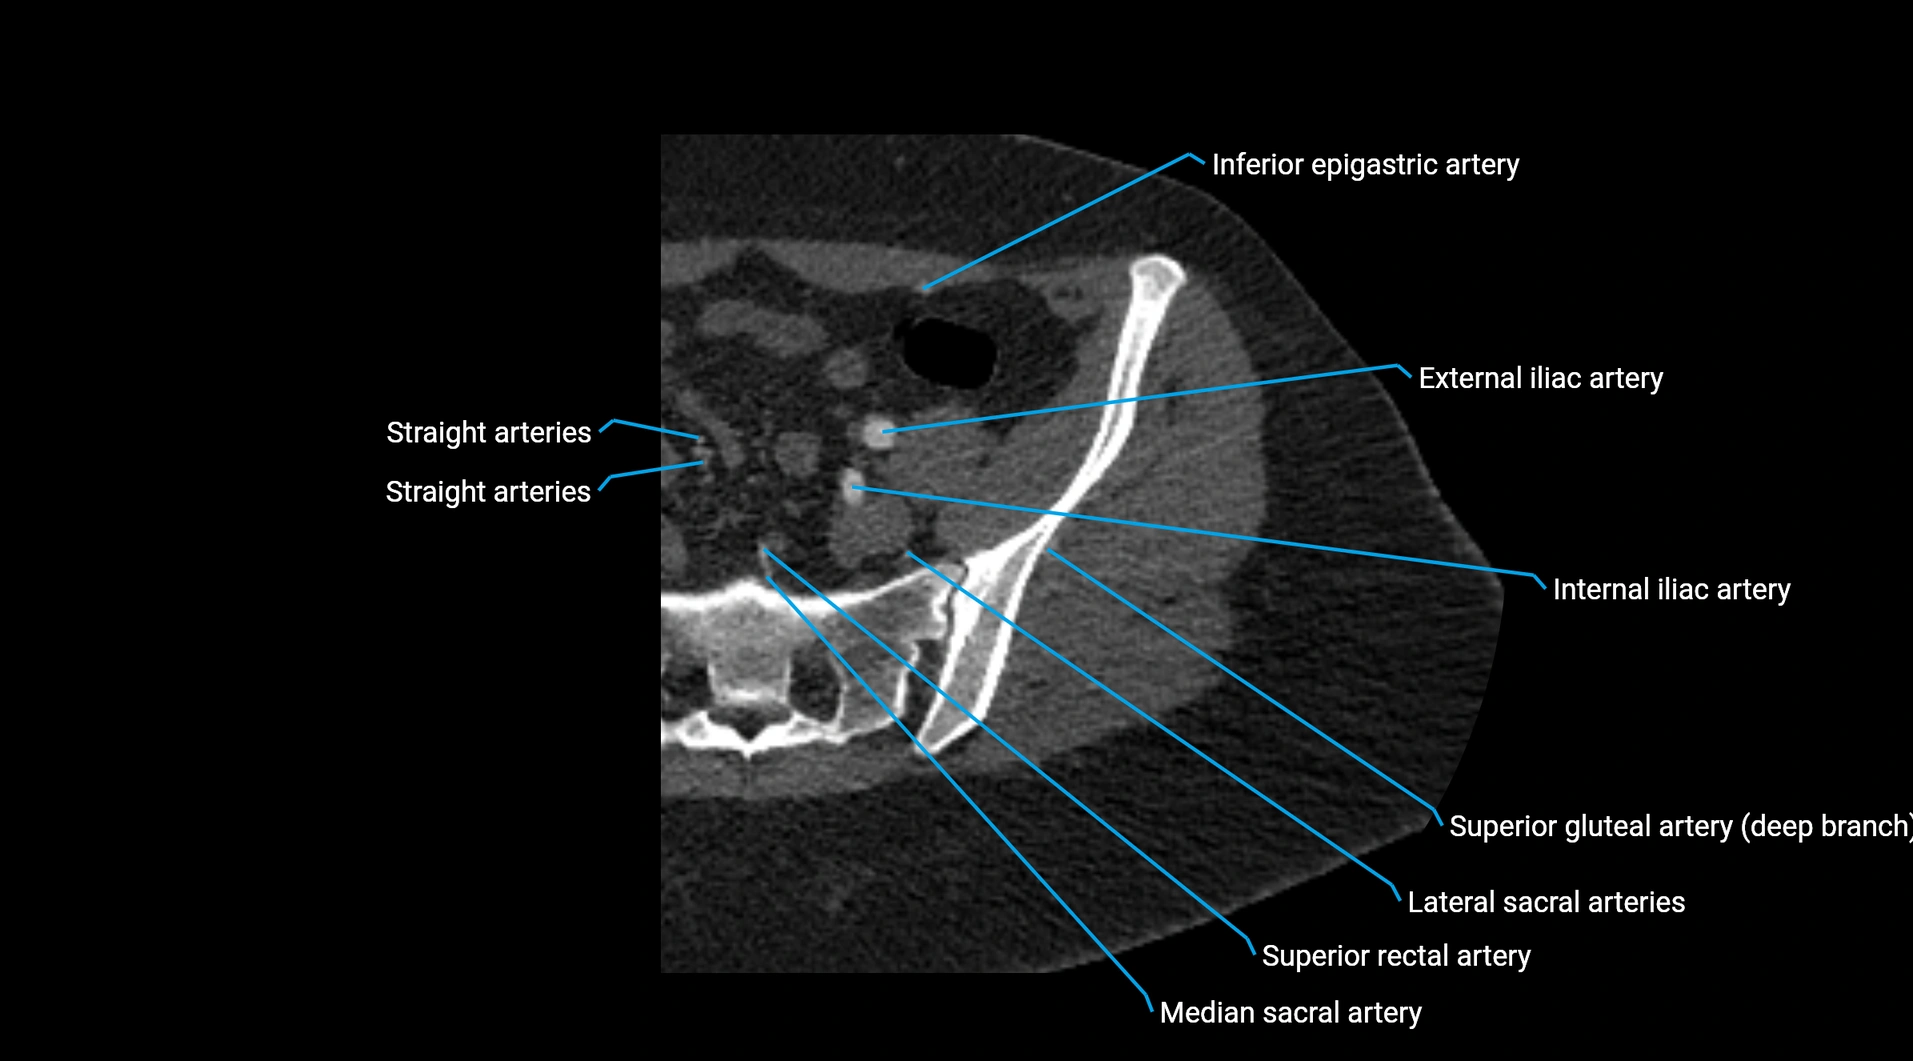

CT images

image